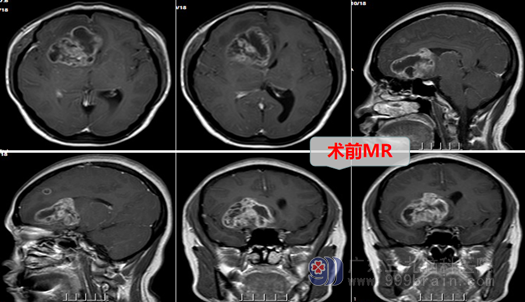

外十科主任欧阳辉教授热情地将她收住院。入院后欧阳主任结合磁共振、CTA等影像资料分析指出:患者右侧额颞岛叶占位性病变,病变范围广、是跨脑叶肿瘤,考虑成人弥漫性胶质瘤,应该尽快做手术。于是外十科团队很快为患者做好了术前准备,于第二天在全麻下行右侧额颞岛叶-胼胝体膝部-基底节区胶质瘤切除术。